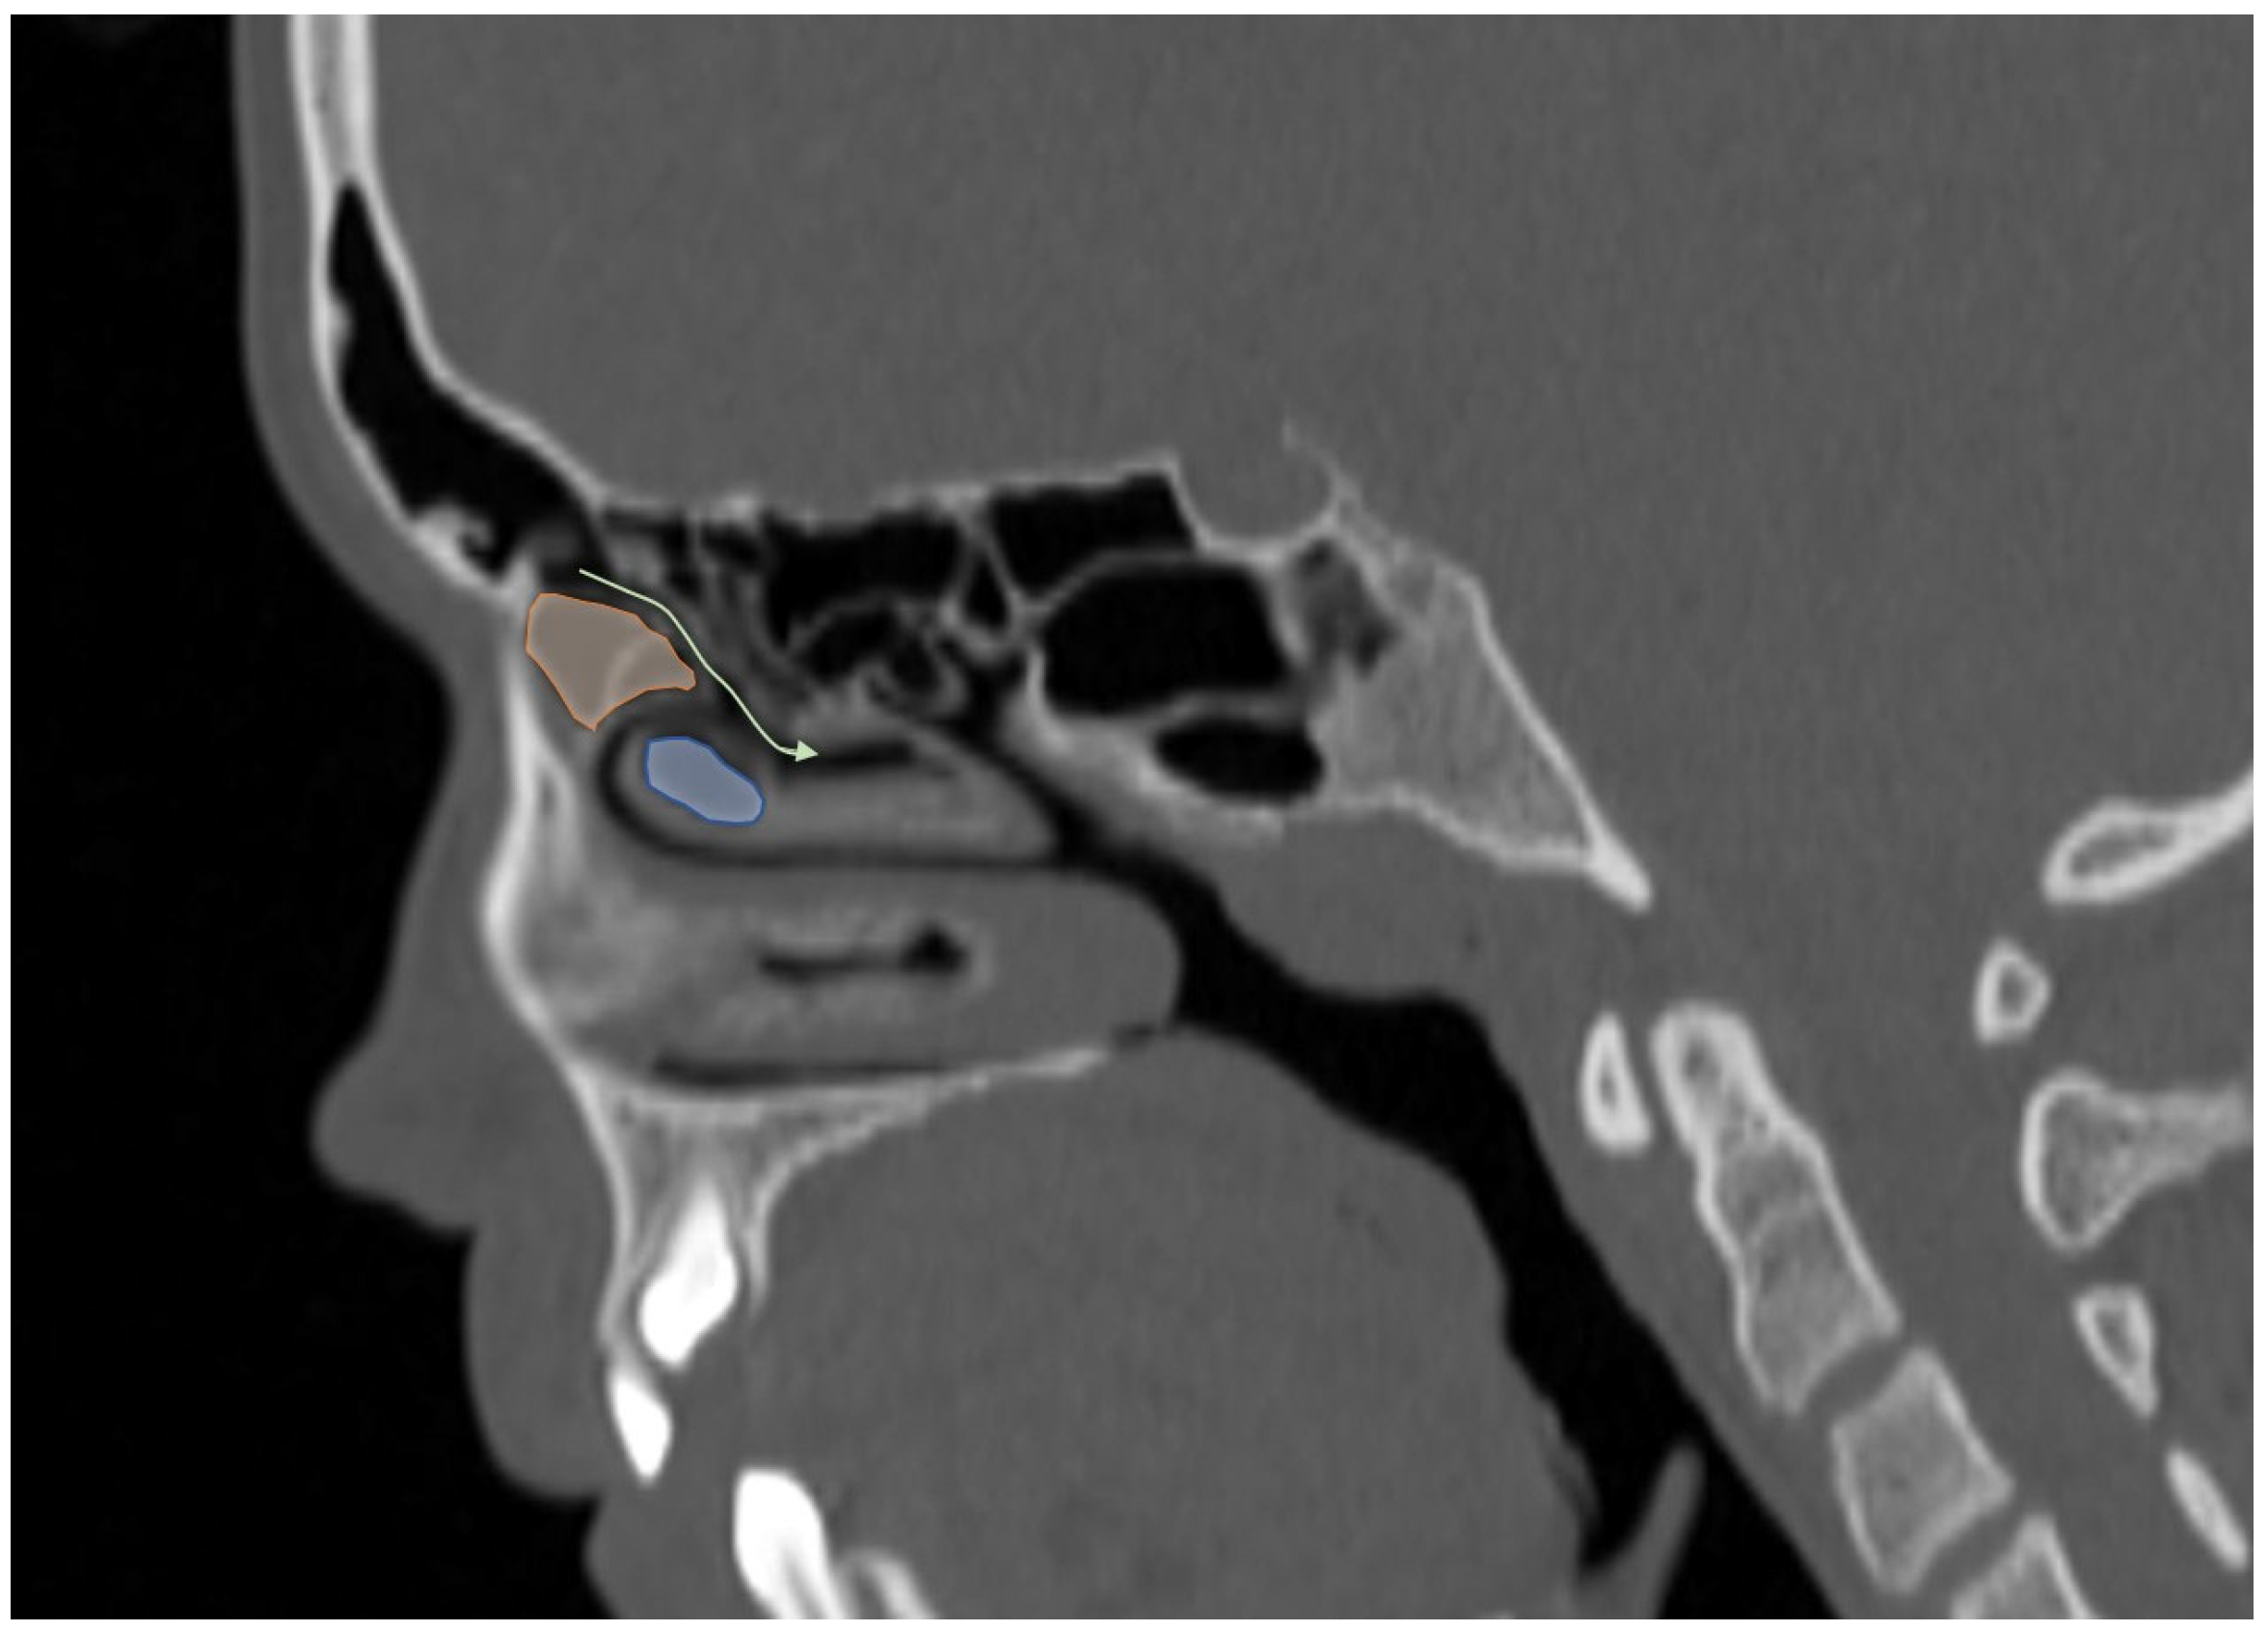

3.2. Sinonasal Variations